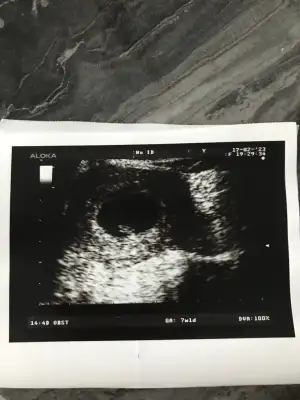

Benim ki nerde ben anlamadımUltrrasonda bakınca yolksacın sağındayı bebek ben ondan yola çıkarak sağ dedim![]()

Ahaha sola doğru yatmış sanki sol diyelim biz benceBenim ki nerde ben anlamadımtam ortada sanki tövbeler olsun akdldldş

Ahhh sol dedinAhaha sola doğru yatmış sanki sol diyelim biz bencemaşallah minnoşa

Meslaa bunda yolk sac nerede tamAhaha sola doğru yatmış sanki sol diyelim biz bencemaşallah minnoşa

Burada yolk sac görünmemiş bebek gözüküyor sadeceMeslaa bunda yolk sac nerede tam